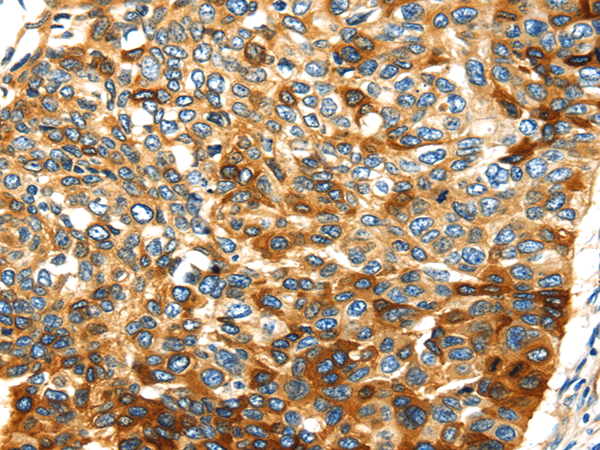

分类: 科研抗体货号: P08790别名: SVAP1; HEL170; SNAP-47; C1orf142; ESFI5812; HEL-S-290应用: IHC反应种属: Human